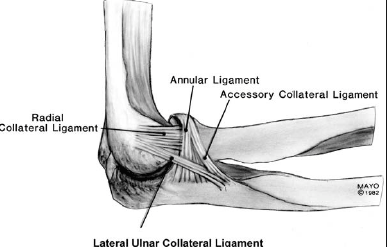

What are the components of the lateral ligamentous complex of the elbow?

Annular ligament

Radial collateral ligament

Lateral ulnar collateral ligament

Accessory lateral collateral ligament - from the inferior margin of the annular ligament to the supinator crest

What are the attachments of the lateral radial collateral ligament?

Lateral epicondyle

Distally, inserts into (blends with) the annular ligament above the equator of the radial head

What are the attachments of the lateral ulnar collateral ligament?

Distally, at the supinator crest of the ulna